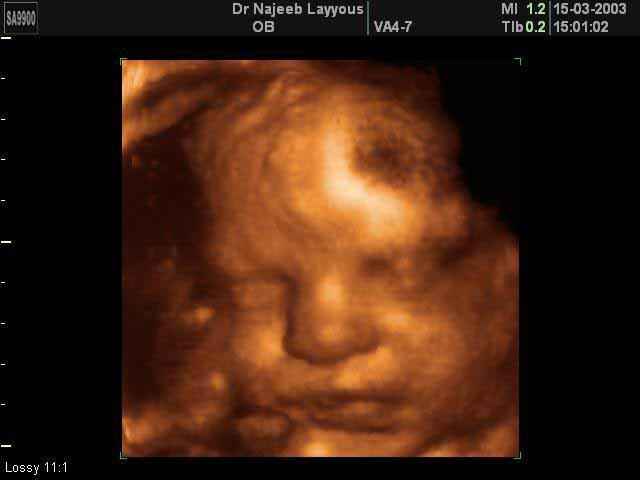

- صور لوجه الجنين في داخل الرحم

صور لوجه الجنين بجهاز الالتراساوند ثلاثي الأبعاد | الدكتور نجيب ليوس